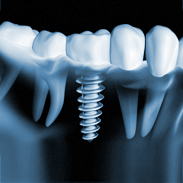

Unter einem Implantat versteht man eine künstliche Zahnwurzel, die von einem Implantologen in den Kiefer eingesetzt wird. Für dieses Implantat werden künstliche Zahnpfeiler hergestellt, sogenannte Abutments, für die dann der eigentliche Zahnersatz konstruiert und angefertigt wird. Die Verbindung zwischen Implantat und Abutment erfolgt durch eine Verschraubung.

Man unterscheidet zwischen festsitzendem Zahnersatz (Kronen und Brücken) und herausnehmbarem Zahn-

ersatz (Totalprothetik oder als Kombination).